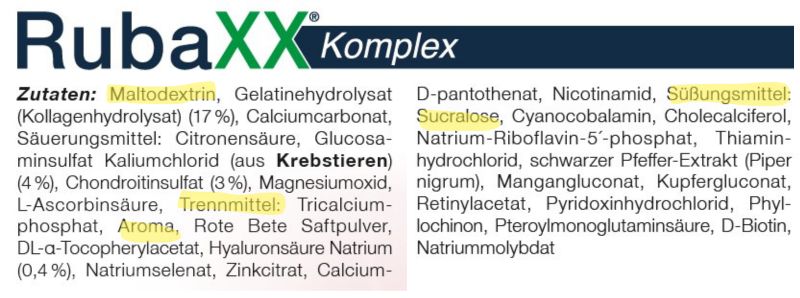

3. Rubaxx Komplex

Platz 3 belegt Rubaxx Komplex vom selben Hersteller. Hier bekommt man ein Pulver zum Auflösen.

Wie vermutet enthält es die Bausteine Kollagenhydrolysat, Glucosamin, Chondroitin und Hyaluronsäure, ergänzt durch viele Vitamine und Mineralstoffe, darunter auch die Co-Faktoren Vitamin C, D, K und Mangan.

Doch hier zeigt die Analyse eine deutliche Schwäche: Eine Wirkfolge für Knorpelschutz, Schmerzlinderung und Knorpelaufbau fehlt.

Und statt der hochwertigen, natürlichen Eierschalenmembran-Matrix setzt es auf die künstlich zusammengestellten Standard-Bausteine (Glucosamin, Chondroitin etc.), deren Bioverfügbarkeit extrem gering ist.

Positiv war der Geschmack des aufgelösten Pulvers für Tester, die auf sehr süße Getränke stehen.

Das führt zu einem weiteren Kritikpunkt – den enthaltenen Zusatzstoffen. Das Pulver enthält Aroma, das künstliche Süßungsmittel Sucralose und Maltodextrin – einen Industriezucker. Zusätze, die Entzündungen sogar verschlimmern können.

Der Beipackzettel zeigt: Erste Zutat Industriezucker (Maltodextrin).

Das Produkt ist relevant durch verschiedene Vitamine, überzeugt einige Tester im Geschmack, zeigt aber trotz PZN ein fehlendes Gesamtkonzept.